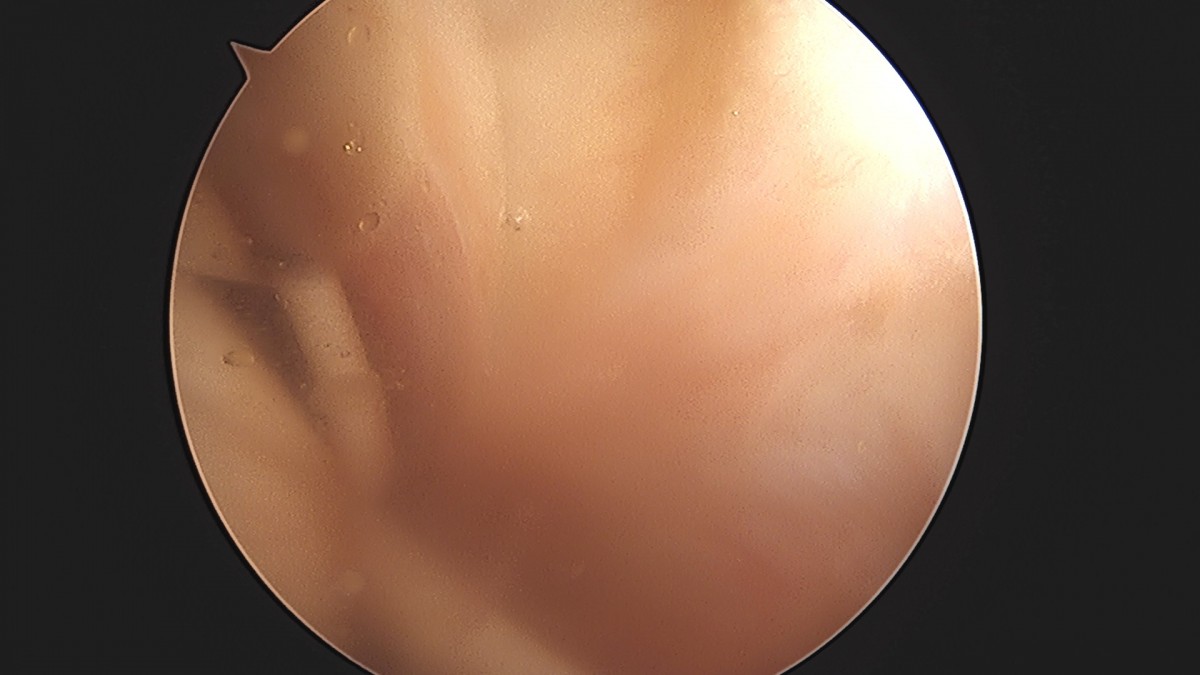

이재상원장님 어깨 견봉하 감압술 및 관절낭 이완술 양명O 환자

작성자 최고관리자 댓글 0건 조회 788회 작성일 25-09-16 15:33